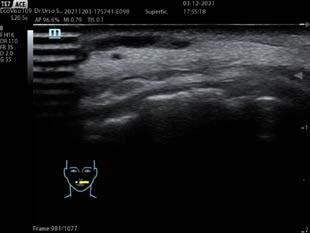

IL CONTROLLO ECOGRAFICO

Un momento clou è stato l’intervento del dottor Piero Fundarò, che ha approfondito l’uso della tossina botulinica off label con controllo ecografico nell’area labiale e perilabiale, più in generale nel terzo inferiore del volto e nel collo. Questo approccio consente di individuare il muscolo bersaglio del trattamento con maggiore precisione, riducendo i rischi e ottimizzando i risultati, in particolare in zone del viso dove è richiesta una gestione molto accurata della tossina. La verifica ecografica del trattamento pianificato offre un monitoraggio in tempo reale. La dottoressa Teresa Lacava ha portato il suo contributo con una tecnica multipunto per la correzione delle rughe fini del prolabio, una zona che spesso viene trascurata, ma che gioca un ruolo

e massima precisione. Questo approccio è fondamentale soprattutto in pazienti che hanno già ricevuto trattamenti in passato, come accade frequentemente nei nostri ambulatori. L’ecografia, infatti, consente di visualizzare le strutture sottocutanee e i materiali eventualmente già presenti, riducendo al minimo la possibilità di complicanze e ottimizzando i risultati finali.

La Masterclass Avanzata sul Trattamento del Terzo Medio del Volto del 26 ottobre 2024 si è aperta con l’in

che ha fornito una panoramica anatomica dettagliata e ha poi fornito un approfondimento sulla tecnica iniettiva per il trattamento del terzo medio del volto. Ha spiegato come le aree zigomatiche-malari siano cruciali per conferire definizione e struttura al viso e come l’uso di filler visco-elastici possa ripristinare i volumi in modo naturale. Il dottor Quercia ha anche trattato la visione estetica globale, enfatizzando come ogni intervento sul terzo medio debba essere parte di un piano di trattamento full face, in cui il trattamento di una sola area non comprometta l’armonia complessiva del viso. Il dottor Simone Ugo Urso, in collegamento da remoto con la dottoressa Molinari, ha proseguito con un focus sull’utilizzo dell’ecografia come strumento diagnostico per una pianificazione precisa del trattamento: permettendo di visualizzare in tempo reale le strutture anatomiche, consente di pianificare le iniezioni in modo sicuro, riducendo al minimo i ridottoressa Paola Molinari ha poi messo l’accento su complicanze durante i trattamenti del terzo medio del volto, come l’ino le reazioni avverse ai filler, mostrando come riconoscere tempestivamente e trattare le complicanze in modo efficace, ma soprattutto come prevenirle anche grazie all’impiego di questa tecnologia in